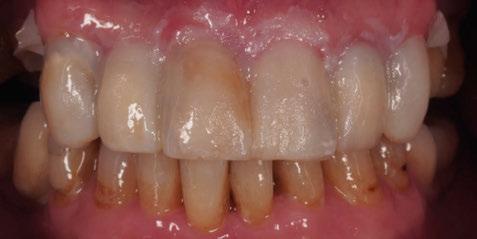

Figura 1a. Foto intraoral frontal inicial.

Figura 1b. Foto intraoral lateral izquierda inicial.